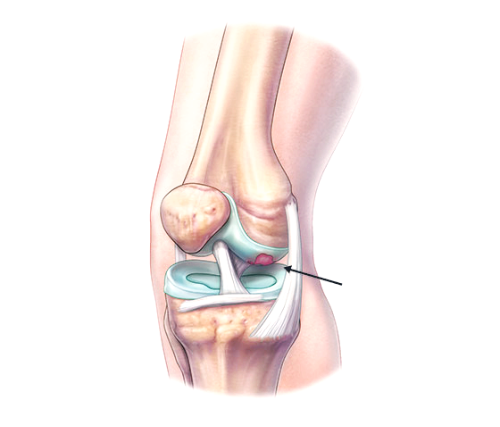

골관절염은 연골에 손상이 가해지면서 관절의 간격이 줄어들고 뼈가 서로 맞닿아 통증을 동반하는 질병입니다. 콘드로이친은 질병과 외부 충격으로부터 체내의 조직을 안전하게 보호하고 동시에 조직 표면에 가해지는 충격 등을 이겨낼 수 있도록 탄성을 주는 프로테오글리칸(Proteoglycan)이라는 물질의 생성을 돕게 됩니다. 때문에 콘드로이친은 특히 골관절염에 효과가 있습니다.

콘드로이틴황산염은 연골 구성 성분의 하나이고 연골세포를 자극해 연골조직을 정상적으로 복원하는데 효능이 있다고 알려져 있습니다. 특히 외부 자극에 의해 문제가 되는 TNF-알파 등 사이토카인의 작용을 억제하는 역할을 합니다. 그리고 지속적인 염증 유발 및 연골 파괴 유발 사이토카인을 감소시켜 관절 내 염증 및 통증반응 그리고 연골파괴를 막아주는데 도움을 줍니다.

콘드로이친은 글루코사민과 같이 연골 성분의 일부로써 연골, 힘줄, 뼈, 각막 등의 신체 결합 주위에 널리 퍼져 있습니다. 관절 연골에 필요한 영양을 공급하고 연골을 분해하는 효소를 억제함으로써 관절 건강에 도움을 줍니다.